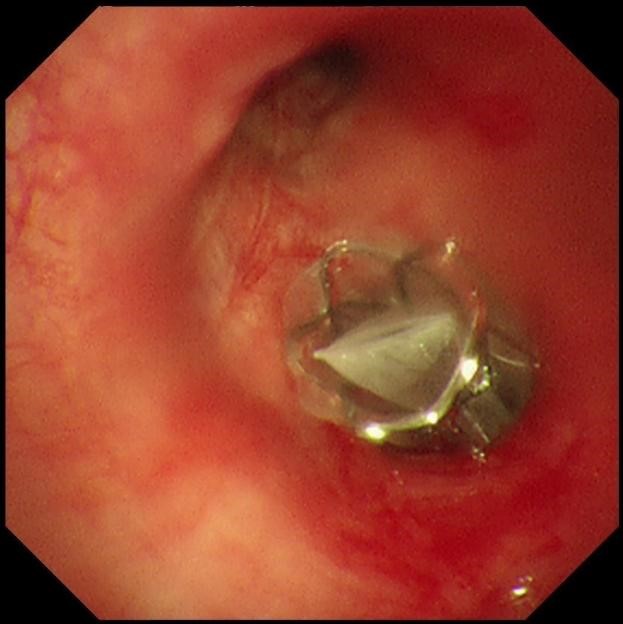

手术当天,蒋军红主任和曾大雄主任密切配合,用时30分钟便顺利完成手术。手术通过微创支气管镜介入,在高清内镜视野下,精准定位病变最严重的靶肺叶支气管,精准植入一枚微型支气管内活瓣(EBV-TS-5.5),术中实时验证活瓣开合状态良好,通气单向引流功能正常。

该技术的核心原理十分精妙:通过支气管镜将特制的微型单向活瓣,精准植入过度充气、丧失功能的病变肺叶支气管内,这个微型活瓣具备“只出不进”的独特功能——吸气时活瓣自动关闭,阻止外界气体进入病变废用肺叶;呼气时活瓣自动打开,让病变肺叶内残留的气体和分泌物顺利排出,从而促使靶肺组织逐渐萎陷、不张,达到肺减容的目的。